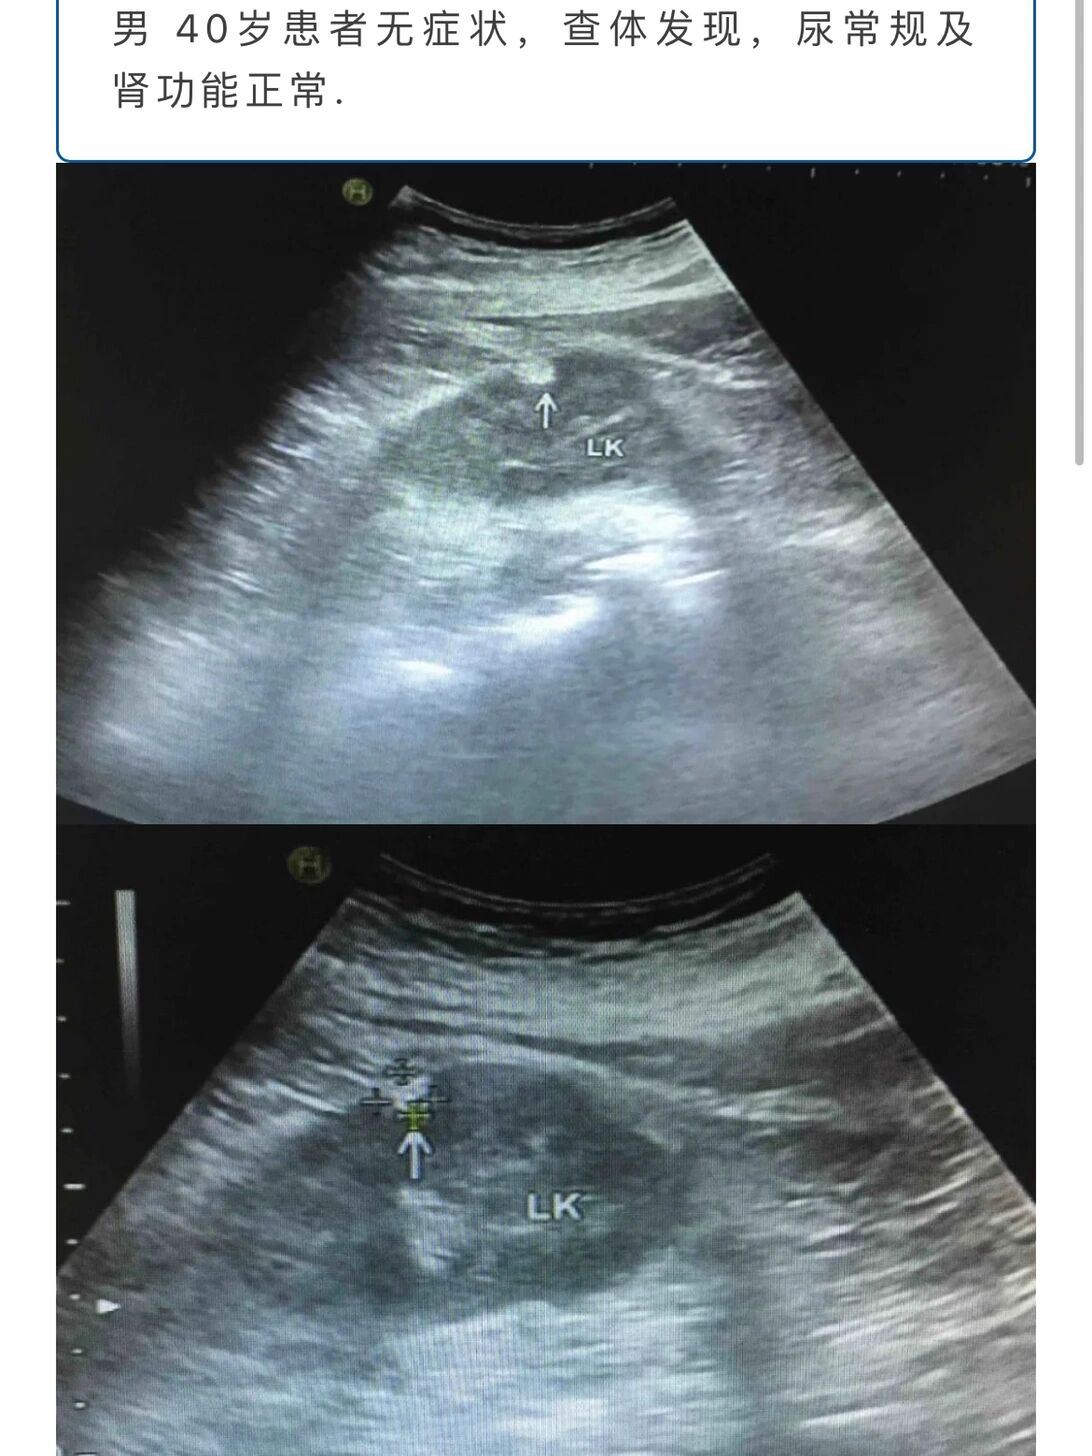

左肾皮质错构瘤